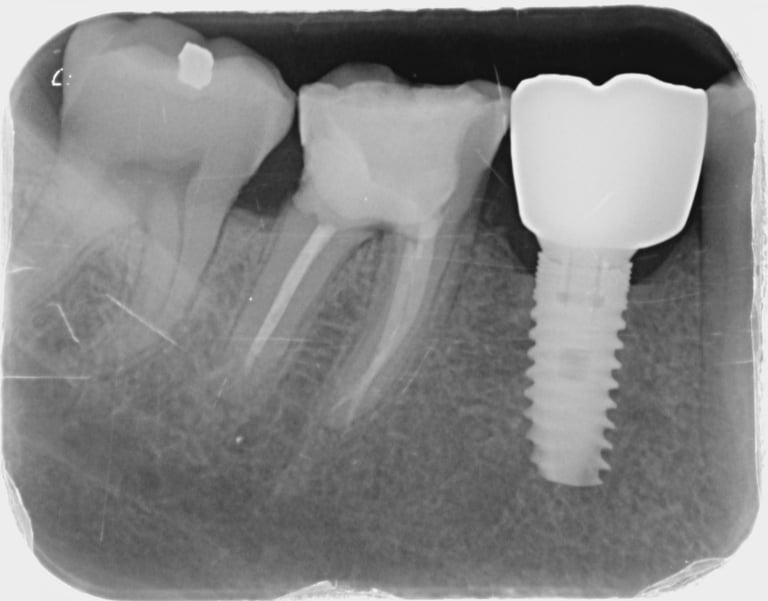

En otros casos, puede ser necesario tomar una radiografía que abarque todo el diente. Estas radiografías se pueden utilizar, por ejemplo, para detectar caries o inflamación en el ápice de la raíz. Se toman, por ejemplo, antes de colocar una corona o en relación con un tratamiento de conducto.